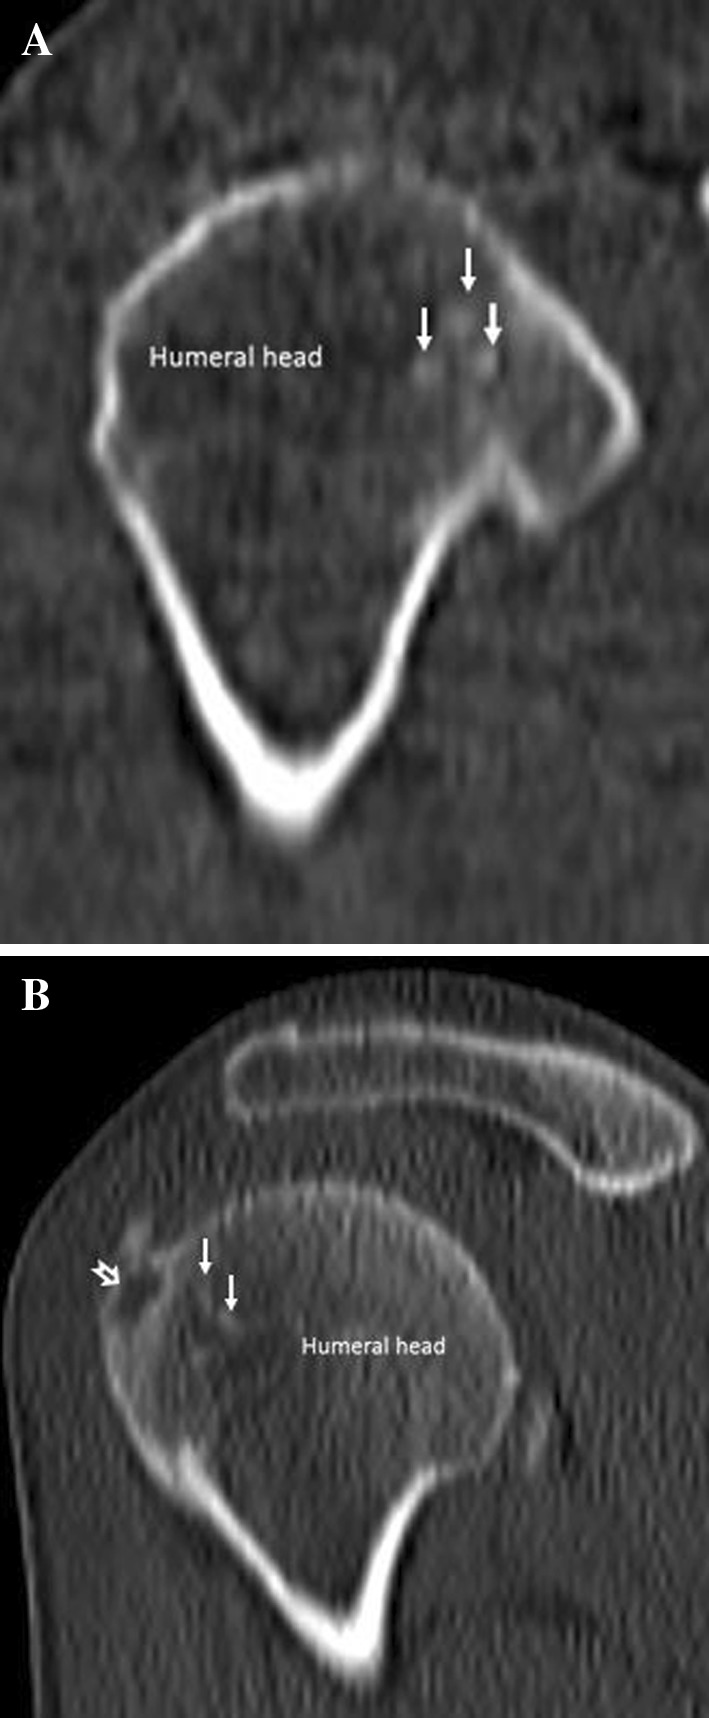

Fig. 5.

Calcium-related osteitis. Coronal (a) and sagittal (b) computed tomography images detect a well-defined rounded lytic lesion of the humeral greater tuberosity (empty arrow in b) and multiple calcifications within the humeral erosion (arrows)

Standard radiographs show focal erosions of the humeral head and a rounded sclerotic intraosseous lesion in the greater tuberosity surrounded by a radiolucent halo; if the calcific deposit has migrated outside the humeral head, plain film shows a rounded well-defined lytic lesion in the greater tuberosity, along with a tendon calcification. CT is the gold standard imaging modality to depict bone lesions (Fig. 5); CTI demonstrates cortical erosion of the humeral head and a rounded well-defined lytic area located in the greater tuberosity; it can also detect calcium deposit in its intraosseous location or in the adjacent tendinous insertion. MRI shows a cystic lesion in the greater tuberosity and the intraosseous/intratendinous calcification; MR is superior in evaluating bone medullary involvement, in fact the bone marrow (Fig. 6) surrounding the cystic lesion of the greater tuberosity presents a typical reactive edema pattern extending from the greater to the lesser tuberosity with a characteristic spare of the cranial part of the proximal humeral epiphysis. Both CT and MR can easily depict a possible tendon-associated tear.